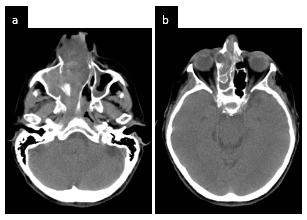

El diagnóstico diferencial de papiloma invertido y otras masas de la fosa nasal es de difícil determinación, siendo necesaria las mediciones densitométricas tomográficas. Los valores densitométricos de la masa en las adquisiciones en nuestro paciente sin contraste se encuentran entre 55 - 60 UH y posterior a la infusión del contraste oscila entre 70 - 80 UH; el cornete medio presenta densidades entre 40 - 45 UH, mientras que las secreciones mucosas muestran valores entre 25 - 40 UH. Si bien estos realces no son específicos para realizar el diagnóstico de papiloma invertido, podrían ser de utilidad para la valoración de la extensión del mismo (Figura 1 – 2).

En la Tomografía sin contraste del macizo cráneo facial se aprecia formación de densidad de partes blandas ubicada en fosa nasal y seno maxilar derecho con extensión a senos frontales y celdillas etmoidales, la formación hace protrusión hacia las coanas y Cavum con marcado realce postcontraste (Figura 3).